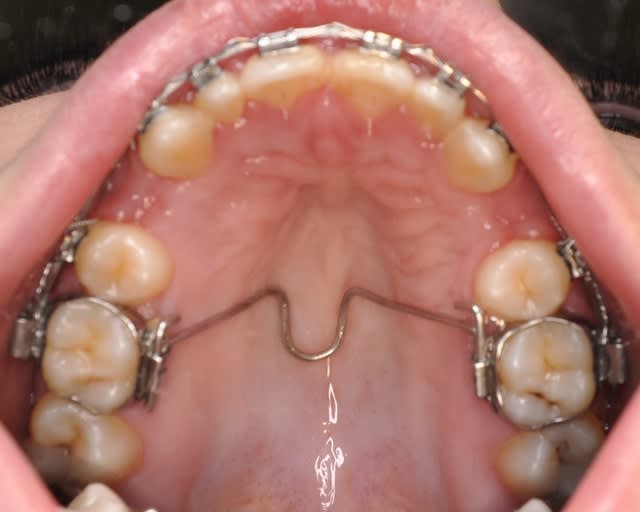

voici la première étape

Dsc 0002 crlur4 - Eugenol

Dsc 0006 h1ilt3 - Eugenol

Dsc 0001 qxvuke - Eugenol

Dsc 0005 pcikt2 - Eugenol